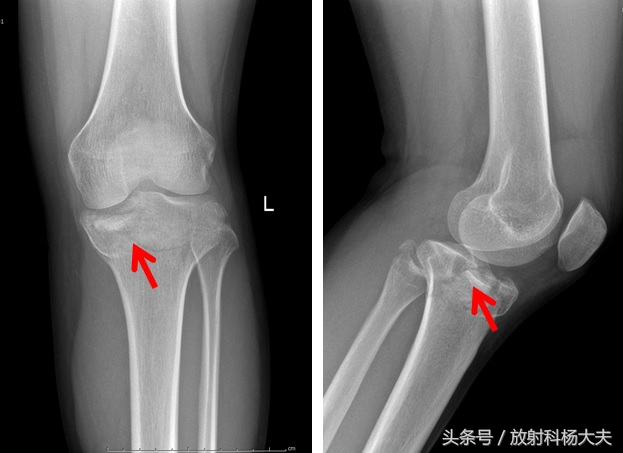

骨折

为何要先拍片子?拍了片子,是看骨头断了没?踢球踢断了骨头,在足球史上是存在的。拍片子是一种非常便捷的手段,可以初步观察有无骨折等,但因为这种损伤,多伴有其他软组织损伤,而且有些隐匿的骨折用平片是看不到的,所以,很多时候,都需要再做MRI。这个检查的选择,受很多因素的影响,需要具体问题具体分析。